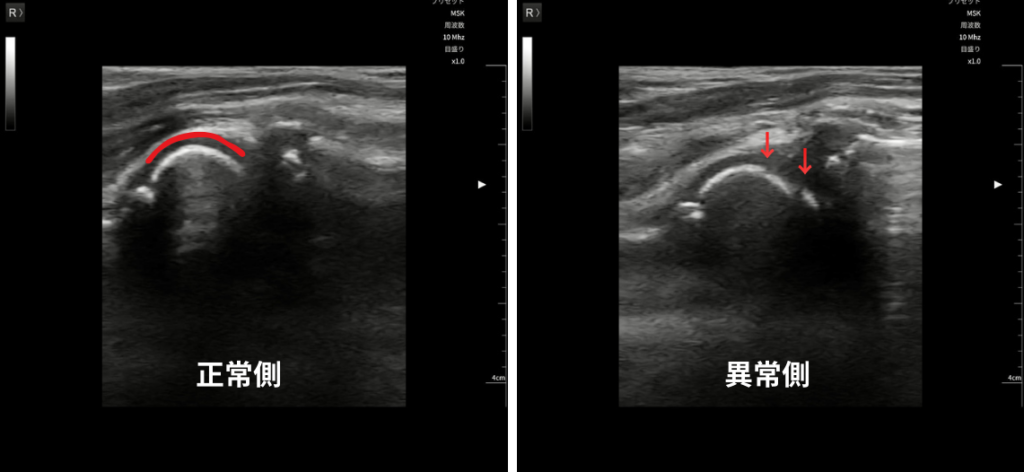

当院で観察した離断性骨軟骨炎の例 ※上部画像のモデルと関係ありません。また矢印部分に障害があることを医師に確認済み。

野球肘専門外来の病院に紹介